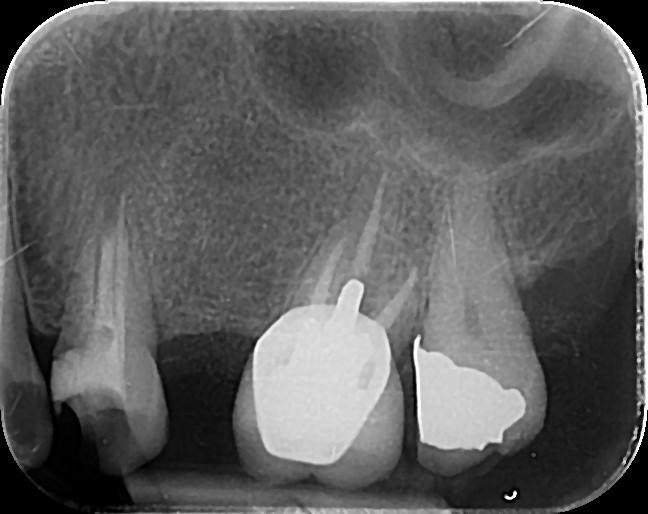

10: What is the caries level on occlusal of the tooth # 2.7?

11. What is the caries level of the distal surface of the toot # 3.5?

18. Which surfaces need restoration?

19. What are the caries level in mesial surface of tooth # 3.8 and distal surface of tooth # 3.7 respectively?